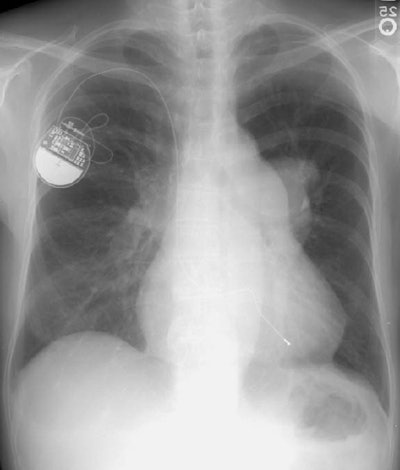

Long-standing Pulmonic Stenosis

The elderly female in the image below had a long-standing history of pulmonic stenosis. There is very prominent enlargement of the pulmonary outflow tract, as well as asymmetric enlargement of the left main pulmonary artery.